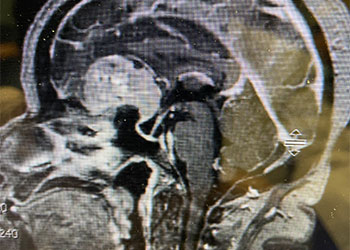

This is a 55-year-old female with no past medical history who presented electively with a 10 month history of progressively worsening mid back pain radiating across the chest, and gait disturbance. Pain was especially worse at night and when laying flat. Her exam was pertinent for severe ataxia when ambulating, and elevated deep tendon reflexes in the lower extremities. She had severe and debilitating symptoms, as demonstrated by her Visual Analog Scale (VAS) and Oswestry Disability Index (ODI) of 9/10 and 64/100, respectively. MRI of the thoracic spine with and without contrast demonstrated a large intradural extramedullary homogenously enhancing mass at T8, resulting in near obliteration of the spinal canal and severe cord compression. She was referred to Dr. Xavier Gaudin for neurosurgical management.